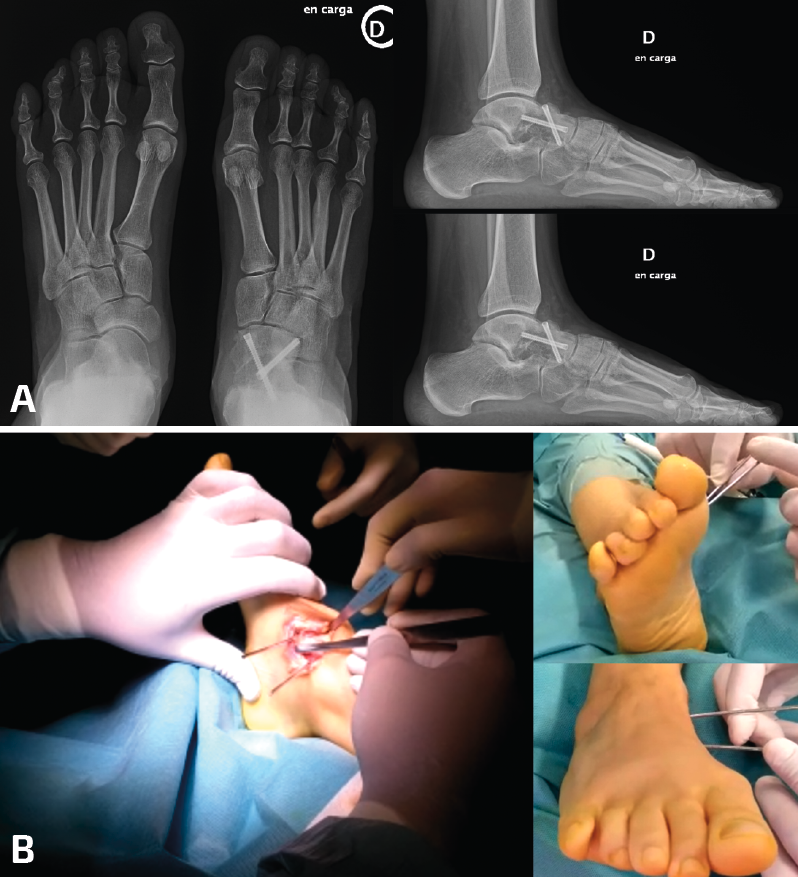

Figura 3. Paciente con mucho dolor en tobillo y región lateral del pie 2 años después de una artrodesis talonavicular por una artropatía postraumática. A: la radiología en carga evidencia una consolidación en varo de la artrodesis, con la columna medial encima (y no al lado) de la lateral, con un callo en el cuarto metatarsiano por lesión de estrés secundaria a la carga anómala; B: osteotomía correctora desrrotatoria en CORA (center of rotation of angulation) talonavicular para conseguir un pie plantígrado. La utilización de 2 agujas permite con facilidad la rotación en el foco de la osteotomía y la orientación espacial de la corrección.

- Demasiado varo: las dobles/triples artrodesis tarsianas son cirugías complejas en las que no es fácil obtener una posición adecuada en el espacio para que el pie funcione plantígrado. El varo iatrogénico es más frecuente que el valgo. Una doble/triple consolidada en varo provocará el daño distal hacia la región lateral del antepié con el resultado de lesiones de estrés sobre el cuarto y el quinto metatarsianos. También existirá una compensación proximal que tendrá que asumir el tobillo que, con frecuencia, presentará dolor medial por sobrecarga y (en ocasiones) inestabilidad anterolateral. El fracaso para diagnosticar el origen de la deformidad en la artrodesis con una consolidación viciosa puede llevar a realizar gestos quirúrgicos erróneos que empeoren mecánicamente el pie. La identificación de un varo en la artrodesis puede verse en la exploración, con un buen análisis visual de la marcha y con el estudio de las queratosis laterales en la región distal y lateral del pie. Unas buenas radiografías en carga nos revelarán muchas pistas directas e indirectas para poder llegar al diagnóstico. Las directas incluyen la apertura del seno del tarso, la posición ortogonal de la subtalar posterior respecto del suelo, la situación de la columna medial del pie encima (y no al lado) de la columna lateral, la visualización completa del cuboides, etc. Las indirectas pueden verse en forma de lesiones sobre el antepié, como la existencia de un callo de fractura en un metatarsiano lateral que nos haga pensar en una fractura de estrés previa por la sobrecarga anterolateral del pie. El tratamiento de esta situación iatrogénica pasaría por la realización de una osteotomía desrrotatoria y la fijación en un valgo discreto mecánicamente adecuado para dejar de sobrecargar el antepié y el tobillo, lo que suele conllevar una mejoría sintomática en el tobillo (Figura 3).